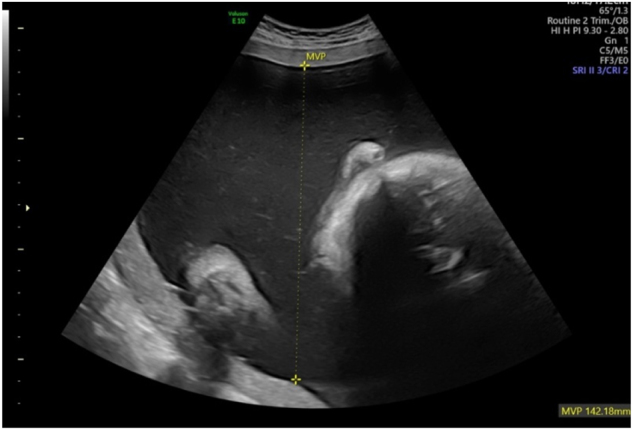

Case presentation: It is the case of prenatally diagnosed cDM. In 32 weeks of pregnancy multiple sonographic findings such as severe polyhydramnios, bilateral talipes, fetal legs akinesia, macrocephaly with mild bilateral ventriculomegaly, right-sided pleural effusion and diaphragmatic pathology were observed by fetal medicine specialist. As the patient complained of weakness in her limbs, she was consulted by a neurologist. The neurological examination revealed a pathognomonic sign of DM1 - grip myotonia. The amniotic fluid and the mother's blood sample were further tested for DM1. This identified >150 repeats in one copy of the DMPK gene of the both, which is consistent with the diagnosis DM1.